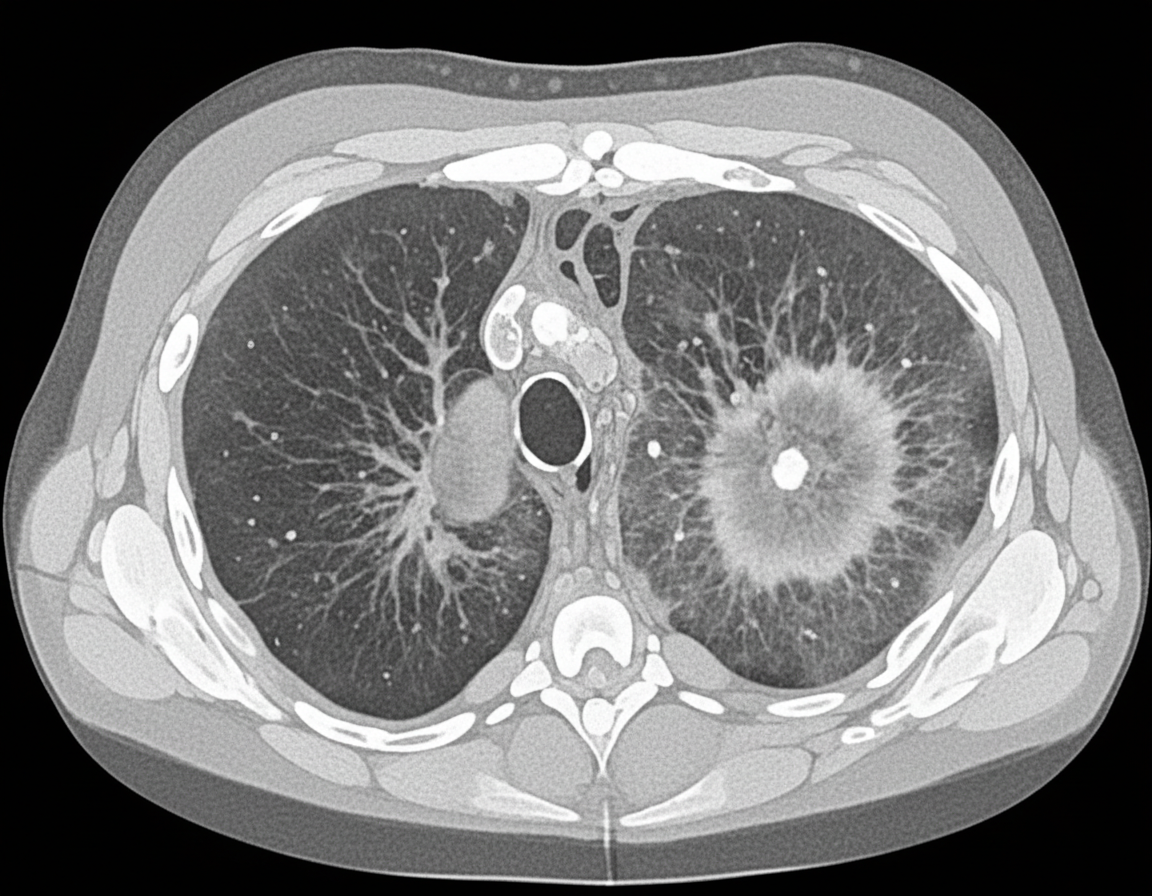

A 26-year-old man is undergoing a bone marrow transplantation for treatment of a non-Hodgkin lymphoma that has been refractory to several rounds of chemotherapy and radiation over the past 2 years. He has been undergoing a regimen of cyclophosphamide and total body irradiation for the past several weeks in anticipation of his future transplant. This morning, he reports developing a productive cough and is concerned because he noted some blood in his sputum this morning. The patient also reports pain with inspiration. His temperature is 101°F (38.3°C), blood pressure is 115/74 mmHg, pulse is 120/min, respirations are 19/min, and oxygen saturation is 98% on room air. A chest radiograph and CT are obtained and shown in Figures A and B respectively. Which of the following is the most likely diagnosis?